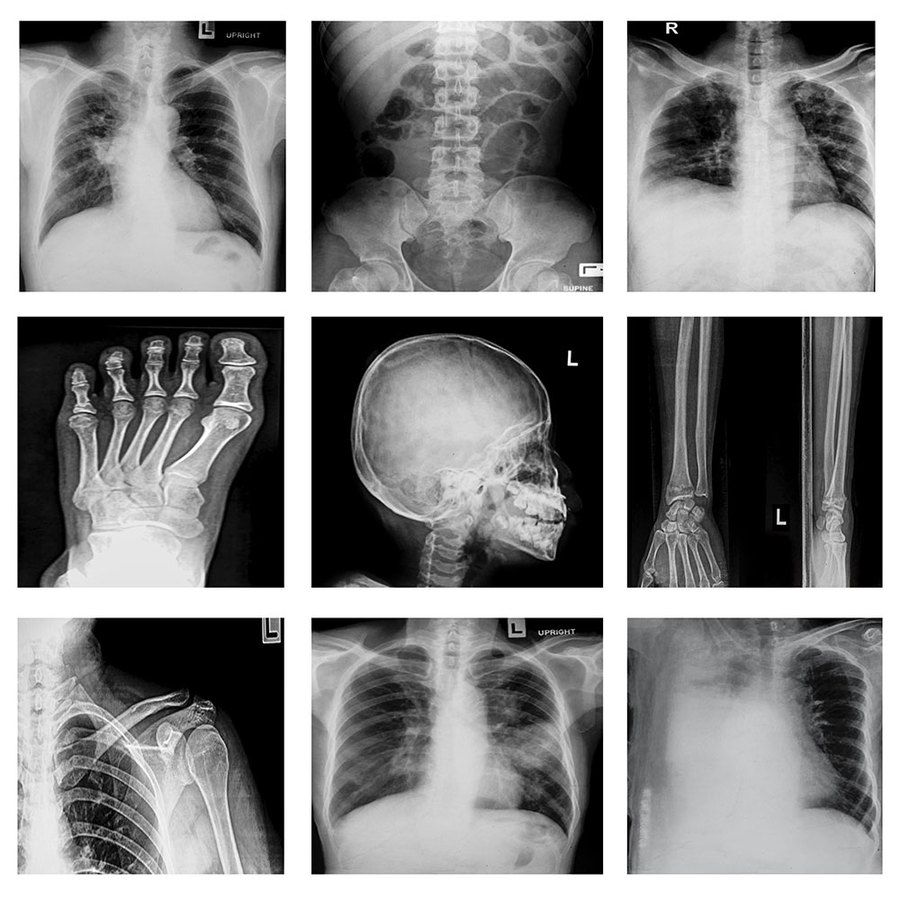

When a bone is fractured, your doctor can take x-rays to determine its severity. These images are not only diagnostically useful, but also potential evidence in a lawsuit. Typically, the parties involved will agree on compensatory damages, which include medical expenses, lost current and future wages, and other out-of-pocket costs.